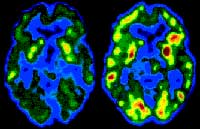

When the same person listens to the same piece of music

first subjectively and then analytically, the right hemisphere is more activated

PET scan of the brain of an alcoholic 10 days (left) and

30 days (right) after the start of abstinence Because

Left: PET scan of the brain of a healthy person. Right:

PET scan revealing lower levels of serotonin (a neurotransmitter) in a person

with severe depression The images produced by PET scans

cannot compete with those produced by fMRI scans in terms of resolution, but often

provide spectacular colour contrasts (the warmer colours represent the more active